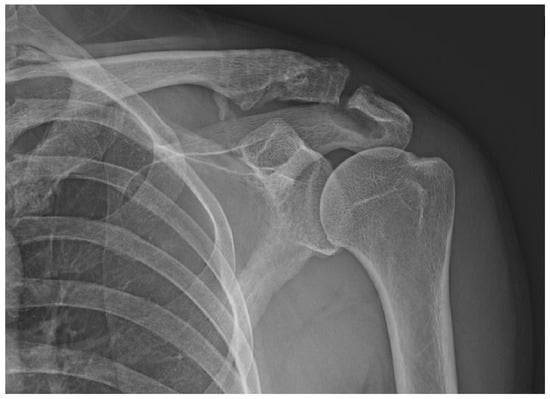

Varying degrees of subacromial erosion occurred in all patients, and acromial fracture occurred in one case in the DCF group and seven cases in the ACD group (Figure 2 and Figure 3). Five (6.7%) cases showed incomplete union and one (1.3%) case showed peri-implant stress fracture in the DCF group (Figure 4 and Figure 5). Four of the five cases of incomplete union showed fracture union without additional surgery during the follow-up period, and one case did not heal at the final follow-up, although the patient did not show any discomfort with non-union (Figure 6). The peri-implant fracture healed with conservative management before plate removal. LOR was observed in nine patients with ACD. Before removing the hook plate, LOR occurred in six patients with ACD. Among these six patients, five showed acromial fracture and one showed serious subacromial erosion (Figure 7). After removing the hook plate, LOR occurred in three patients during the follow-up period. However, none of these patients with LOR among patients with ACD showed tenderness on the acromioclavicular joint or pain during the follow-up period. Regarding acromial fracture, one (1.3%, 1 of 36) case was observed in the DCF group and seven (8.3%, 7 of 33) cases were noted in the ACD group (Figure 4). There was no difference in the incidence of acromial fracture between patients with DCF and ACD (p = 0.066). All eight patients had fracture union without additional surgical treatment during the follow-up period.

Figure 4. Incomplete union. (a) A 57-year-old male patient 4 months after hook plate fixation. (b) The plate is removed after incomplete union on patient request. (c) Bone union is achieved during follow-up.

Figure 6. The only case of non-union among five incomplete union cases. (ac) A 50-year-old male patient is fixed with a hook plate and bone union is not completed at 4 months, but severe painful shoulder stiffness is noted; therefore, manipulation is performed while removing the metal plate. (d) Bone union does not occur during the follow-up period.